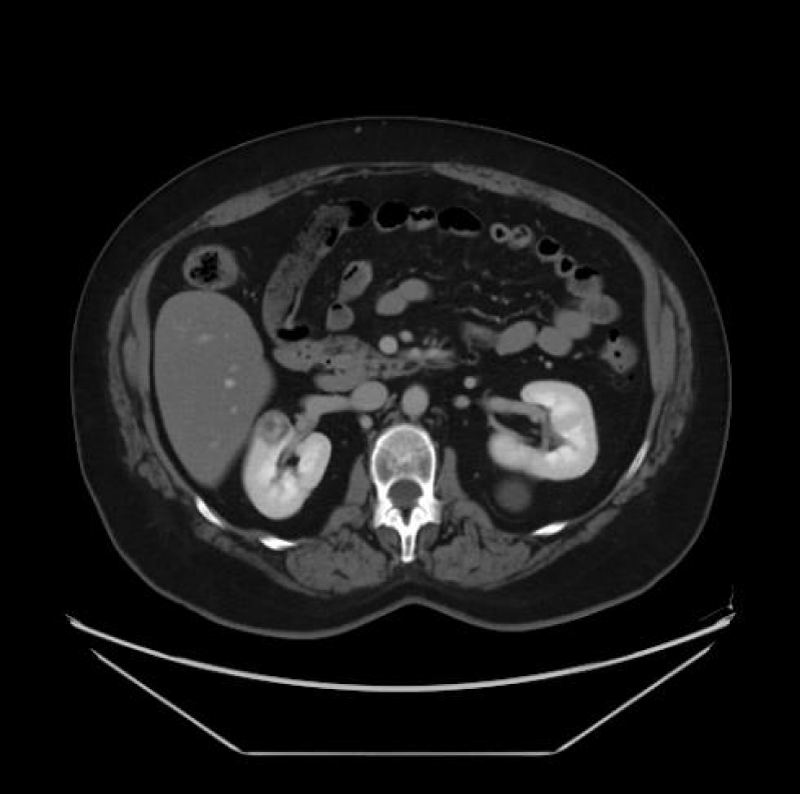

Renal cell carcinoma (RCC) is the ninth and fourteenth most common carcinoma in men and women respectively, alongside being the most lethal urological malignancy. RCC accounts for up to 90% of all kidney cancers, and up to 80% of all SRM. RCC constitutes Clear Cell (Figures 4-6), 75%, Papillary, around 15% to 20%, Chromophobe (Figures 7-9), 5% and other rarer subtypes. Clear Cell is the most common variant with the worst prognosis as it commonly presents at an advanced stage. Papillary type is more frequent in smaller lesion sizes [1,2,3,9-15].

Download Image

Figure 4: Clear Cell RCC of the upper pole of the right kidney.

Figure 5: Left renal Clear Cell RCC.

Figure 6: Right renal Clear Cell RCC.